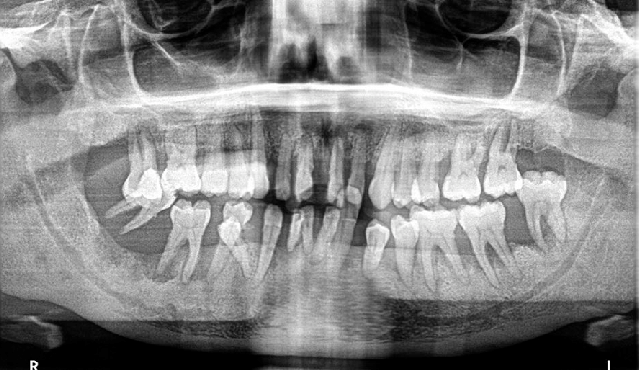

진단을 하기 위해서 반드시 엑스레이 촬영이 필요합니다. (건강보험 적용 가능!)

'당연히' 잇몸뼈의 높이를 확인하기 위해서 입니다.

출처 : ASK A DENTIST

일반적으로 CEJ 라고 불리우는 치아의 머리와 뿌리의 경계에 이르는 만큼 잇몸뼈 높이가 유지되고 있어야만 하지만, 만성치주염으로 인해 잇몸뼈가 소실되면 이 높이를 잃어버리게 되고 왠만한 것은 치과용 파노라마 사진에서 캐치해낼 수 있죠.

그리고 더 나아가 잇몸뼈 소실이 심해지면, 병적인 치아이동 (pathologic migration)도 확인할 수 있게 됩니다.

임상적 경험과 방사선 사진 그리고 시진을 통해서 잇몸치료의 시기와 종류를 정하게 됩니다.